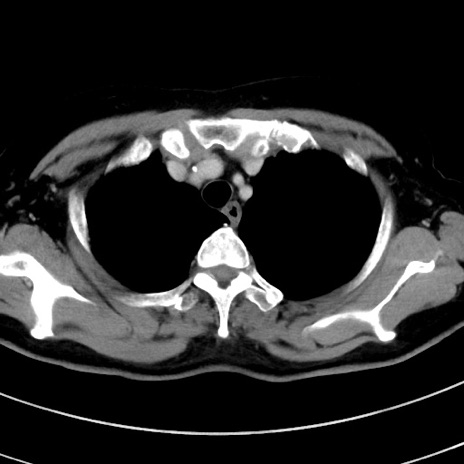

症例9(横断像)

【症例】 60歳代女性

【主訴】むかつき、みぞおちの痛み

【現病歴】3日前よりむかつきがあり、食事がとれない。

【既往歴】糖尿病

【身体所見】発熱なし、心窩部圧痛軽度あるも、腹膜刺激症状なし。

【データ】WBC 7400、CRP 1.92